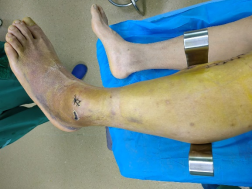

術(shù)前外觀照片